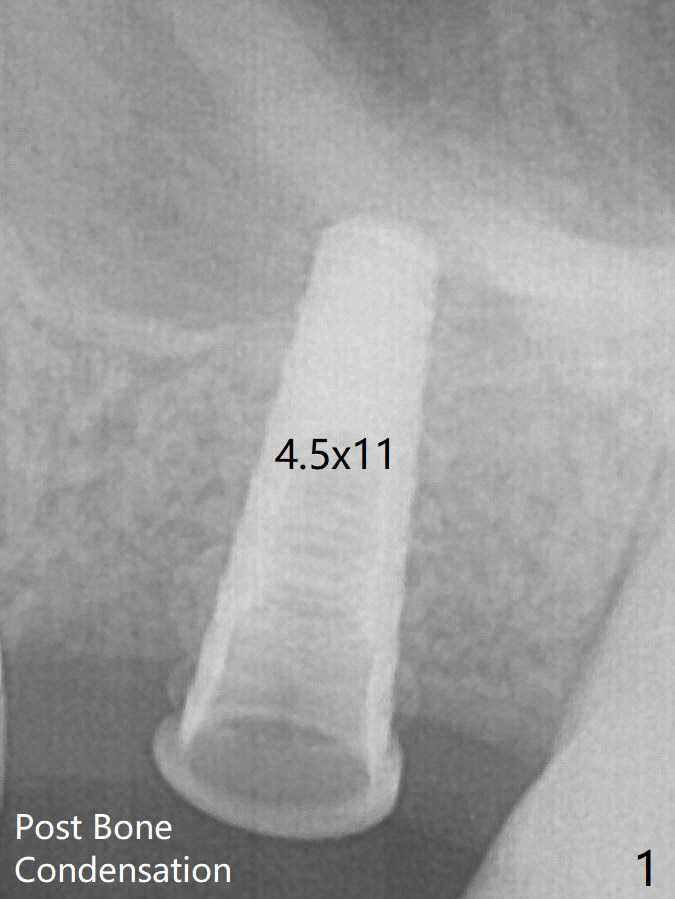

The patient returns 9 months post extraction/socket preservation (Fig.3). The ridge is wide at #14 11 months post socket preservation. Access and bone expansion (BEB) starts with Magic Split, followed by Magic Expanders 3.0, 3.8 and 4.3 mm from 8 to 9 mm for sinus lift. No bone is removed for osteotomy. Instead bone condensation occurs. After placement of a 4.5x11 mm dummy FC implant (Fig.1 with sinus lift), a 5x9 mm Magicore is placed with >55 Ncm with cuff margin at the gingival margin (Fig.2); a 5.5x3 mm solid abutment tries in. There is no occlusal clearance; trimming of the solid abutment will be needed.